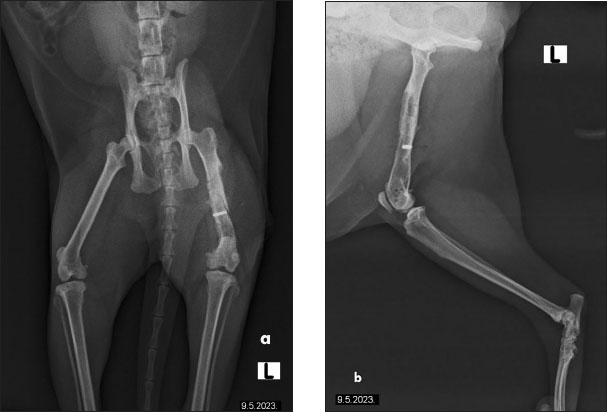

The cat had undergone orthopedic surgery 4 years ago, during which a plate was placed due to a femoral fracture (Fig. 2). Despite the surgery, the patient continued to show signs of discomfort, necessitating further diagnostics and therapy. During the examination at the radiology clinic, the cat showed signs of lameness and pain. The clinical examination revealed muscle atrophy of the left leg and pain on extension and flexion. Radiographic imaging of the pelvis and left femur revealed changes associated with the implant. Removal of the implant was recommended and subsequently performed. Figure 3 shows the radiographs of the cat’s left femur post-plate removal, showing 1 screw remaining in situ. Increased transparency in the medullary cavity indicates the need for LT to enhance healing and promote tissue regeneration.

Fig. 2. The radiographs of a cat’s left femur show (a) a ventrodorsal and (b) a mediolateral view following fracture repair using a 6-hole plate. The fracture is not visible, indicating satisfactory healing. Bone transparency is observed in the medullary cavity of the femur, further enhancing visualization of the internal bone structure. The plate is properly aligned, with no signs of complications.

Fig. 3. Radiographs of a cat’s left femur showing (a) a ventrodorsal and (b) a mediolateral view post-plate removal, with one screw remaining in situ. Increased medullary cavity transparency highlights the need for LT to support bone healing and tissue regeneration.